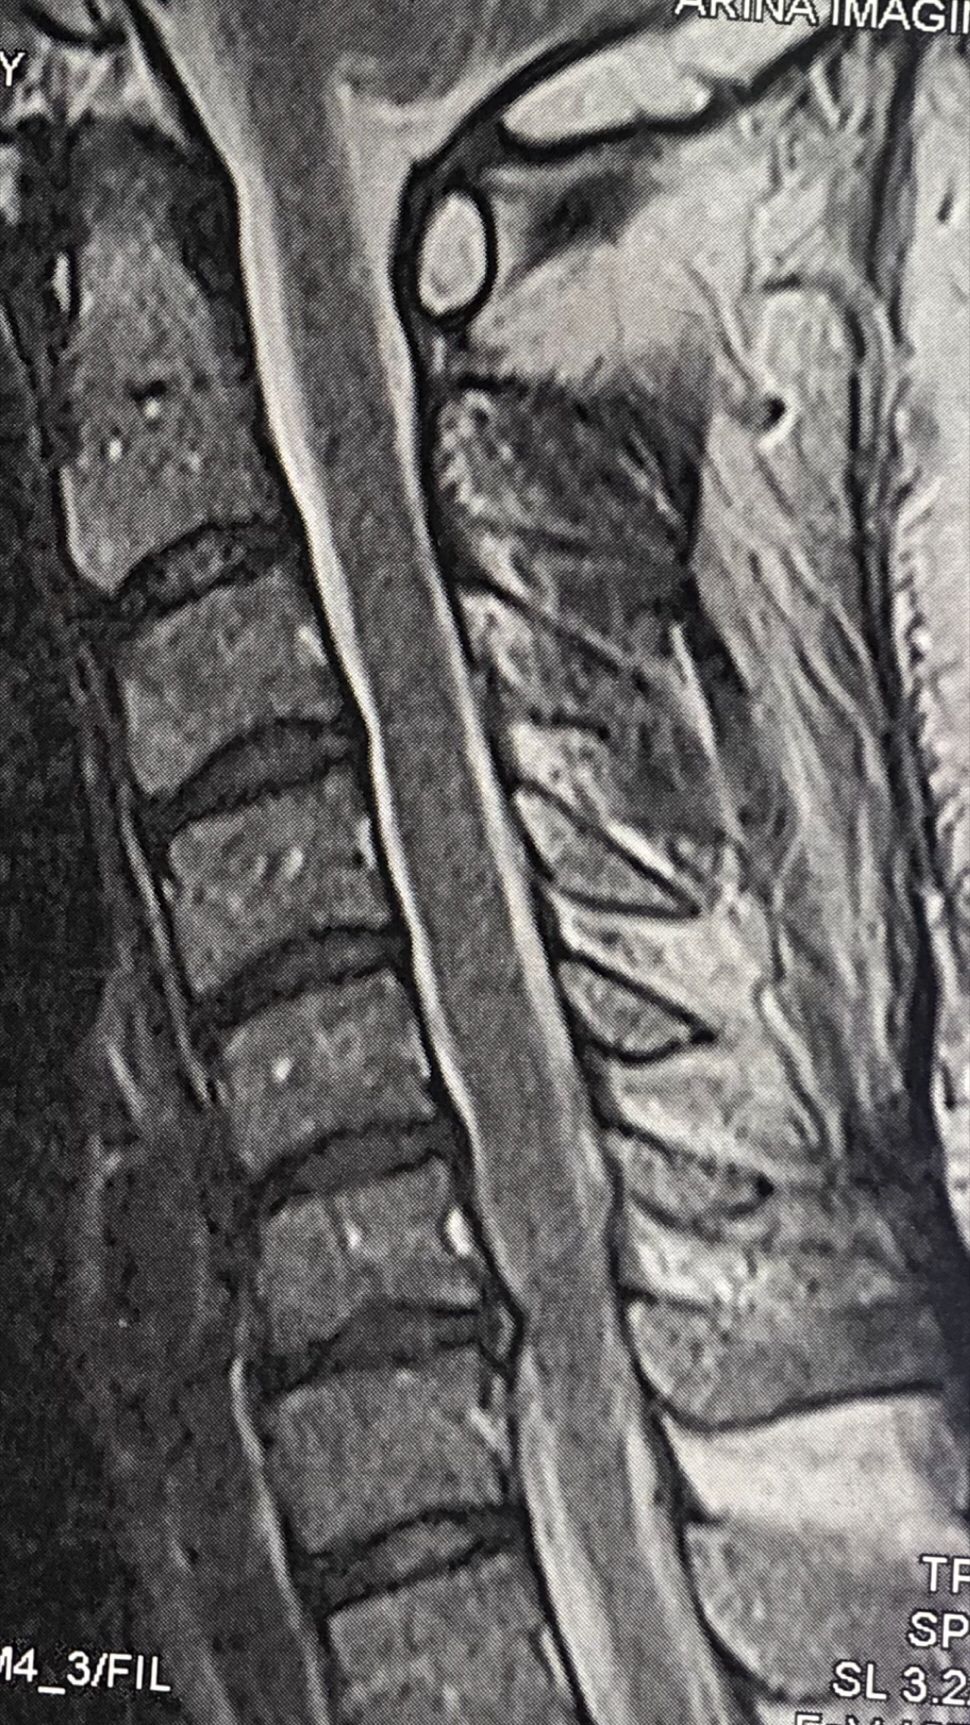

41 years old man presented to my clinic in October 2023 with acute and sever R neck pain with radicular pain to his R upper extremity along C6 dematom since 2 weeks ago. Examination didn’t show any upper motor signs. Was suggested urgent surgery

I ordered EMG/ NCV : showed mild R C6, C7 irritation without any active axonal loss

In his MRI was reported R. para R. IVF Massive extrusion. I decided to control his pain and manage this patient with reevaluation of patient every other session. For 5 sessions i just used acupuncture and laser and IFC and mild adjustments to his R. T3-T7 and mild arthosteem to above and below involved segment. Cervical adjustment considered contraindicated for this patient. From session 6th- 8th i started to use mild/gentle cervical decompression. He used soft cervical collar all the time. His pain decreased by 80 percent

I gave him cervical traction pump to be used 3-5 times per day at home for the next 3 months and i released the patient. He was evaluated every week once for one month and after that every 2 weeks. After 3 month I repeated MRI. Size of the herniated disc was reduced greater than 50 percent. Asked him to do another mri in 6 months

In general: Precise selection of the patients, examination,diagnosis, plan of management, reevaluation and treatment can be done by doctors of chiropractic for the patients with spinal disc herniation and stenosis Moreover giving reasonable time to these kind of patients under direct supervision by their chiropractic doctors can prevent unnecessary surgery. Proper selection of these kind of patients is another important fact that can be done precisely by chiropractors.

MRIs before and after proper management of this patient: